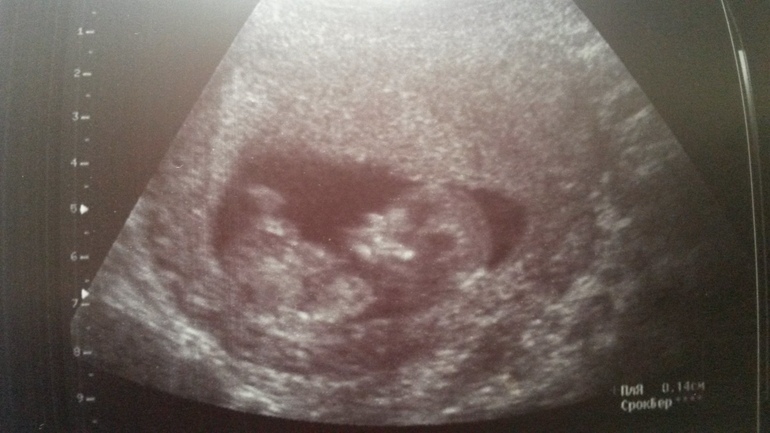

Кроме того, что произвели все необходимые замеры, так еще и рассмотрели все в подробностях :) Боже...уже видно и носик, и зачатки зубов...и все пальчики на руках и

ногах... Малышастик и ручками помахал, и глазки потер, и чего только не вытворял! Удивительно, внутри меня бурная жизнь...А снаружи даже незаметно пока, для шевелений тоже рановато. С Дэни в 14 почувствовала, и то все у виска крутили - мол, для первородящей нереально.

Но для меня самое поразительное было, когда он принял вот эту...до боли знакомую позу :))

Именно в такой позе у меня уже пребывают на диване двое мужиков :)) Дэнька на УЗИ тоже два раза был застукан лежащим вот так - нога на ногу :) И ведь это...в 12 недель! Вот ведь гены, а! Пальцем точно не раздавишь))

По УЗИ все у нас прекрасно :) ЧСС до 156 уд/мин. (Посмотрела, с Дэни на 1-м скрининге было 158 уд/мин). КТР в 11нед.6дн. 51,9мм, БПР 14,1мм, ТВП 1,4мм (при норме от 0,8 до 2,4мм).